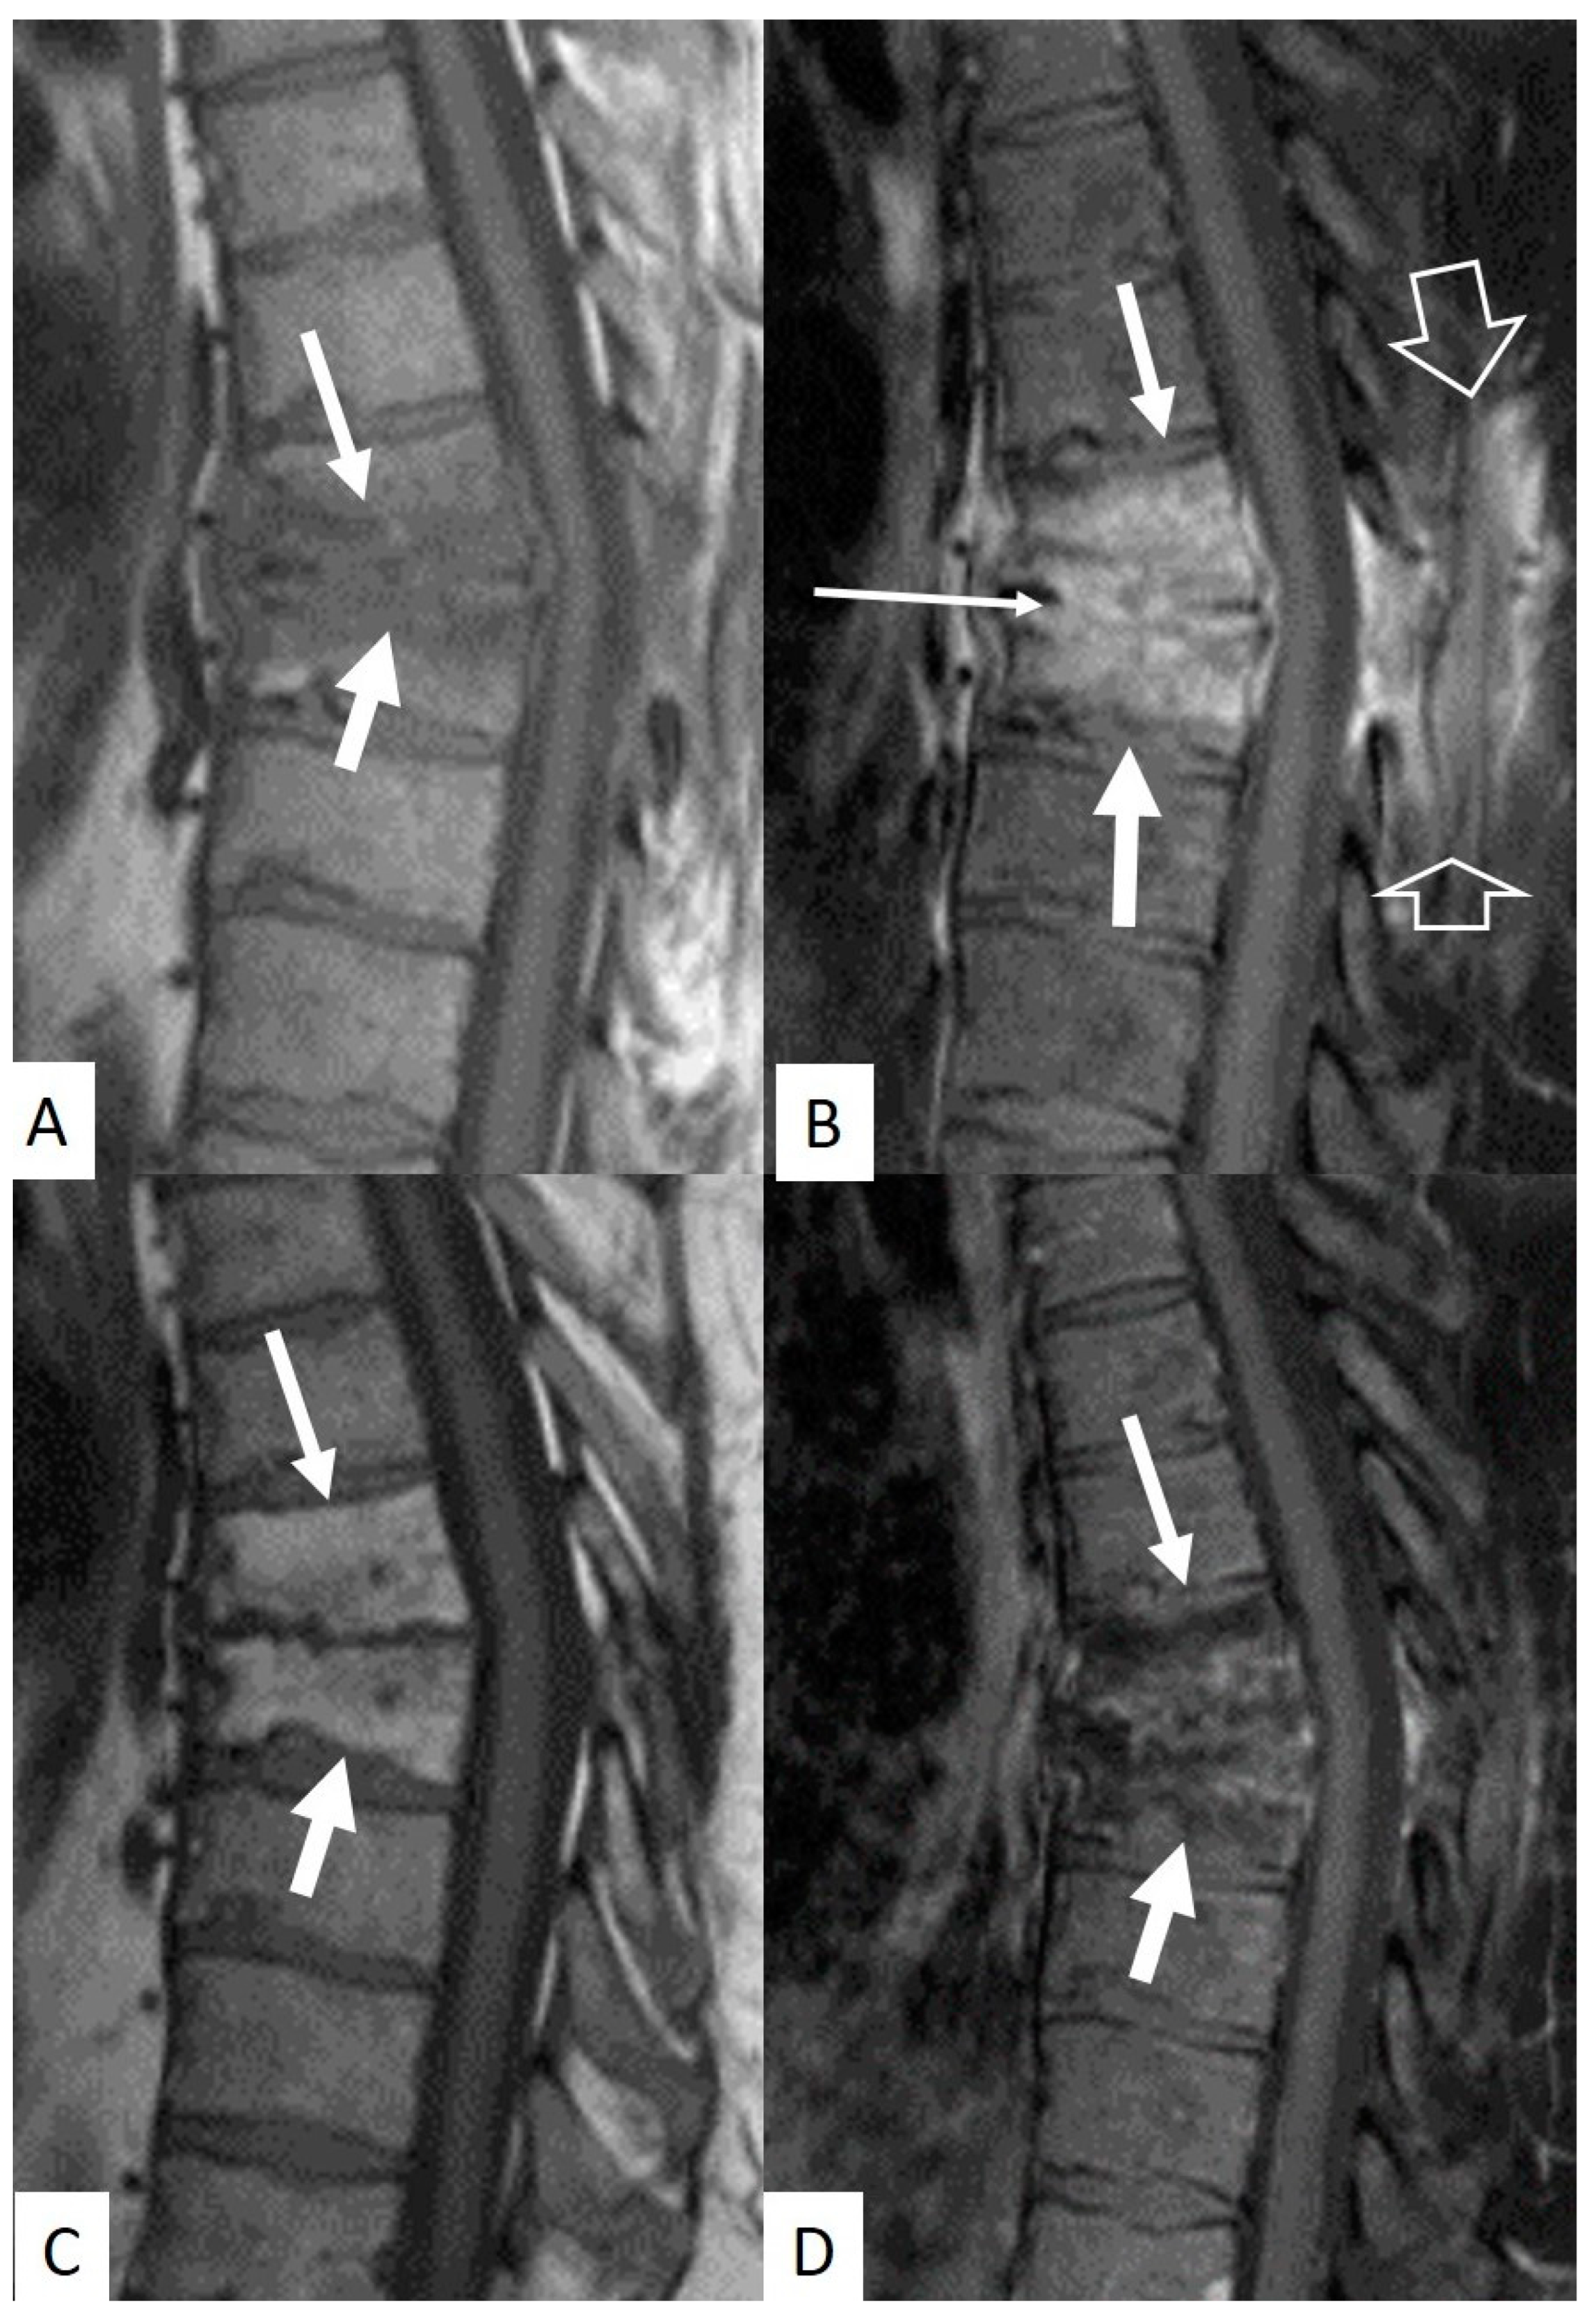

3.4. Imaging